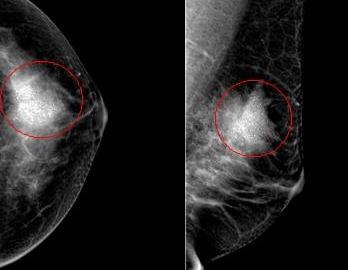

악성 미세석회화의 특징

악성 미세석회화는 다음과 같은 특징을 보입니다.

- 크기가 작고 미세함

- 불규칙한 모양과 크기

- 군집성(5개 이상이 한 곳에 모여 있는 형태)

- 선형 또는 분지형 배열

- 시간이 지남에 따라 수와 분포의 변화가 있음

이러한 특징을 가진 미세석회화는 유방암 또는 전암성 병변과 연관될 가능성이 높습니다. 특히 비침윤성 유관암(DCIS)이나 침윤성 유관암의 초기 단계에서 이러한 형태의 미세석회화가 자주 관찰됩니다. 따라서 이러한 소견이 보이면 추가 조직검사와 적절한 치료가 필요합니다.